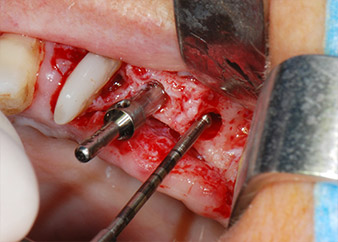

Le sedi di impianto sono state preparate in corrispondenza dei siti 25 e 26 con strumentazione rotante, utilizzando un manipolo contrangolo con una velocità di trasmissione 20:1 con motore potente di nuova generazione (Implantmed di W&H) (Fig. 8).

La preparazione finale vicino al seno mascellare è stata ancora una volta eseguita con uno strumento piezoelettrico (Piezomed, attacco S2).

Prima del posizionamento dell'impianto, e in seguito a verifica dell'integrità della membrana schneideriana (Fig. 9), il seno mascellare interno è stato rialzato in corrispondenza di entrambi i siti di impianto mediante materiale xenogenico di sostituzione ossea (Bio-Oss, Geistlich Biomaterials) (Fig. 10).

La sede dell'impianto è stata preparata con un nuovo motore per impianto (Fig. 20), in combinazione con un manipolo contrangolo progettato specificamente per chirurgia e implantologia odontoiatrica.

La velocità di trasmissione 20:1 e l'elevata coppia del motore dell'impianto, fino a 6,2 Ncm, hanno permesso una preparazione, un inserimento dell'impianto e una maschiatura a bassa velocità. La preparazione finale fino alla membrana del seno mascellare è stata ancora una volta eseguita con l'unità piezoelettrica e uno strumento diamantato arrotondato.